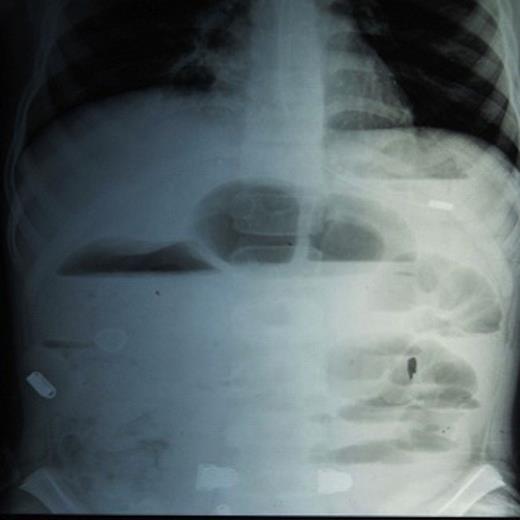

USS examination showed features of intestinal obstruction with ascites. CT revealed small bowel obstruction with minimal fluid collection. On exploratory laparotomy, gut loops were found to be adherent and encased in a membrane (Fig.2).

Intra operative Snapshot showing adherent gut loops encased in a membrane.